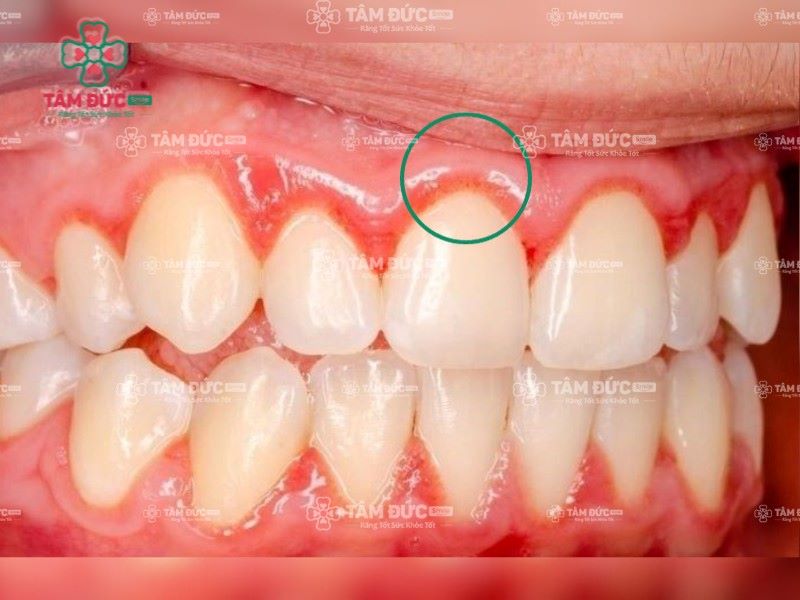

Viêm lợi là một trong những bệnh lý viêm nhiễm ở khoang miệng, làm nướu sưng đỏ và chảy máu. Tình trạng này bắt nguồn từ sự tấn công của vi khuẩn trong mảng bám, hoặc do cao răng tồn tại trong thời gian dài gây ra. Khi không được điều trị đúng cách, viêm lợi sẽ nhanh chóng tiến triển thành viêm nha chu.

Cao răng là một trong những nguyên nhân gây viêm lợi chân răng